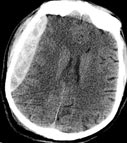

Recent bleeding (subdural hematoma) in an injured patient is seen as a bright mass that is pushing the brain to the other side.